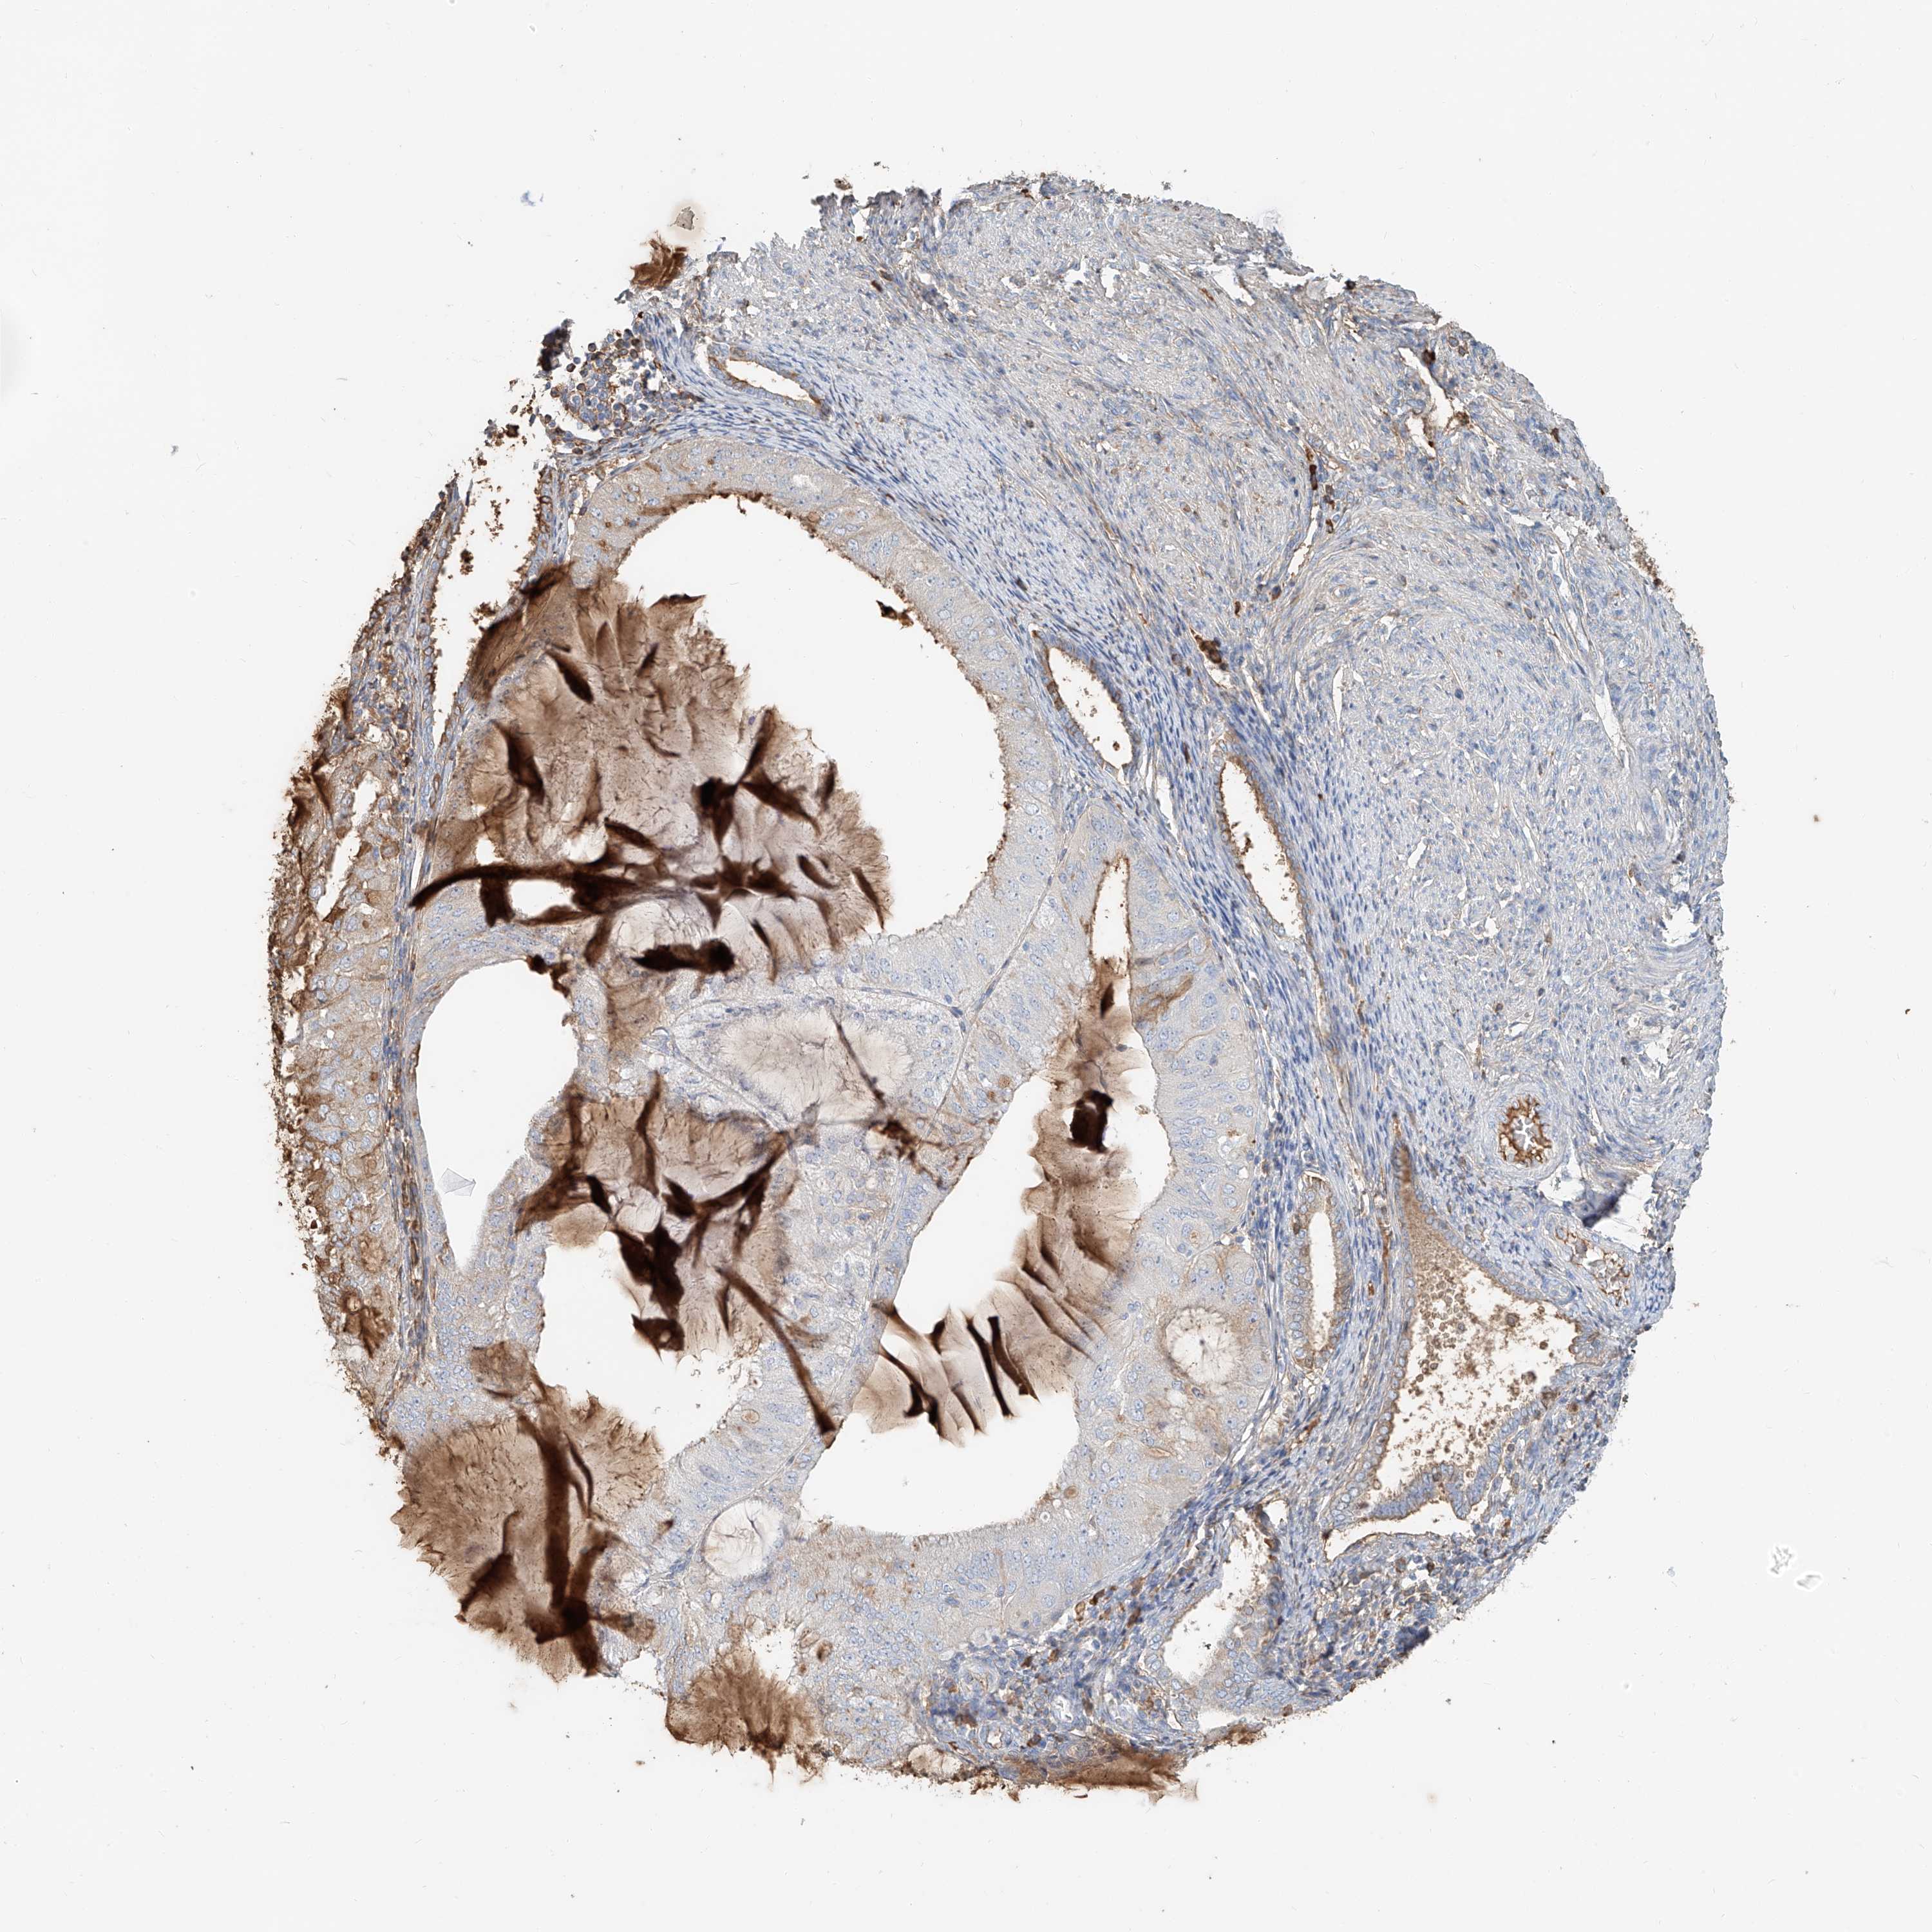

ENDOMETRIAL CANCER - Protein expressioni

A mouse-over function shows sample information and annotation data. Click on an image to view it in a full screen mode. Samples can be filtered based on level of antibody staining by selecting one or several of the following categories: high, medium, low and not detected. The assay and annotation is described here.

Note that samples used for immunohistochemistry by the Human Protein Atlas do not correspond to samples in the TCGA dataset.

Antibody stainingi

Antibody staining in the annotated cell types in the current human tissue is reported as not detected, low, medium, or high, based on conventional immunohistochemistry profiling in selected tissues. This score is based on the combination of the staining intensity and fraction of stained cells.

Each image is clickable and will lead to virtual microscopy that enables deeper exploration of all samples and also displays staining intensity scores, fraction scores and subcellular localization as well as patient and tissue information for each sample.

Antibody HPA030606

Staining

High

Medium

Low

Not detected

Intensity

Strong

Moderate

Weak

Negative

Quantity

>75%

75%-25%

<25%

None

Location

Nuclear

Cytoplasmic/membranous

Cytoplasmic/membranous,nuclear

Adenocarcinoma, NOS

Adenocarcinoma, metastatic, NOS